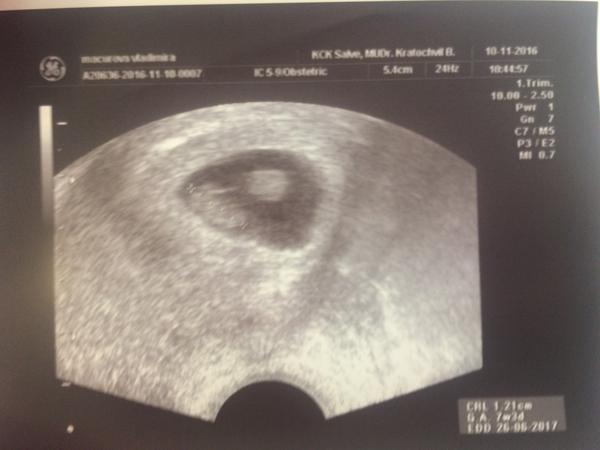

Je na ultrazvuku v 6. týdnu jedno nebo dvě miminka?

Predpokladam ze je to zltkovy vak alebo proste smuha. ja som mala takyto utz a bolo to jedno dieta 😁 dr by vedel